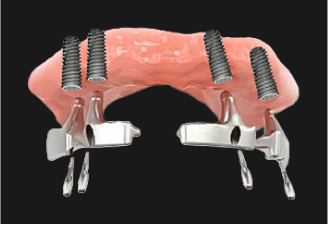

기존 틀니의 단점인 저작 시에 유발되는 잇몸 통증과

자주 탈락되는 장치의 불편함을 보완하고, 임플란트의 기능성을

결합하여 잃어버린 치아기능을 회복시켜주는 치료방법입니다.

구강내 식립된 임플란트가

틀니를 잡아주는 역할을 하여,

자연치아의 70~80% 정도의

저작력을 발휘합니다.

완전 틀니를 할 경우

잇몸뼈 손실이 발생할 가능성이 높지만

임플란트 틀니는 손실 가능성을

최소화 할 수 있습니다.

입천장을 덮는 완전 틀니에 비해

이물감이 적어 일상생활에서도 음식을

섭취하는데 편안함을 느낄 수 있습니다.

1단계 치아상태에 따른 2~6개 정도의 임플란트 식립

2단계 임플란트와 틀니를 연결하는 장치 부착

3단계 제작된 틀니 연결장치에 장착하여 고정